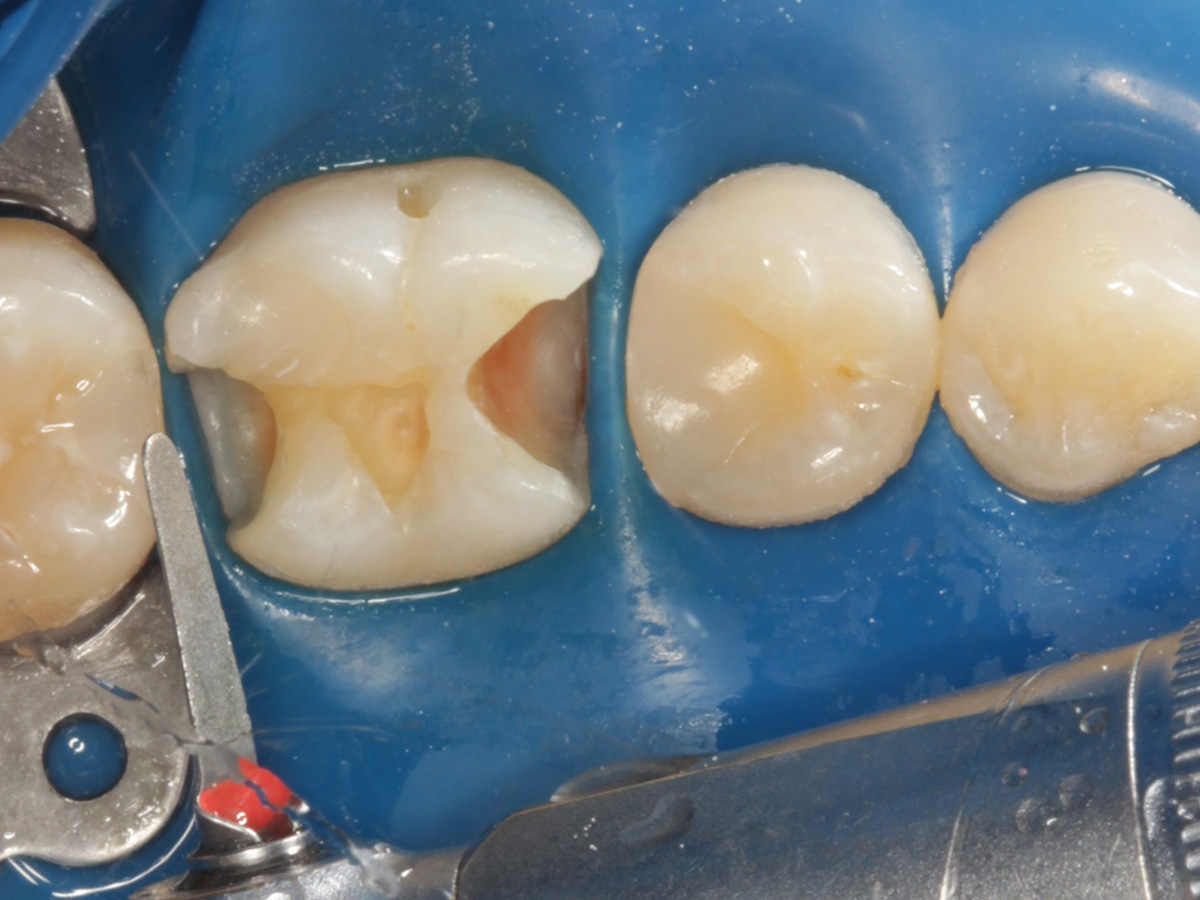

Kavitäten gefüllt (Injektion Moulding: Flowkomposit, erwärmtes Seitenzahnkomposit aus Karpule)

Abbildung 20

Abbildung 21

Zahnseidenkontrolle: kein Überschuss, satte Kontaktpunkte